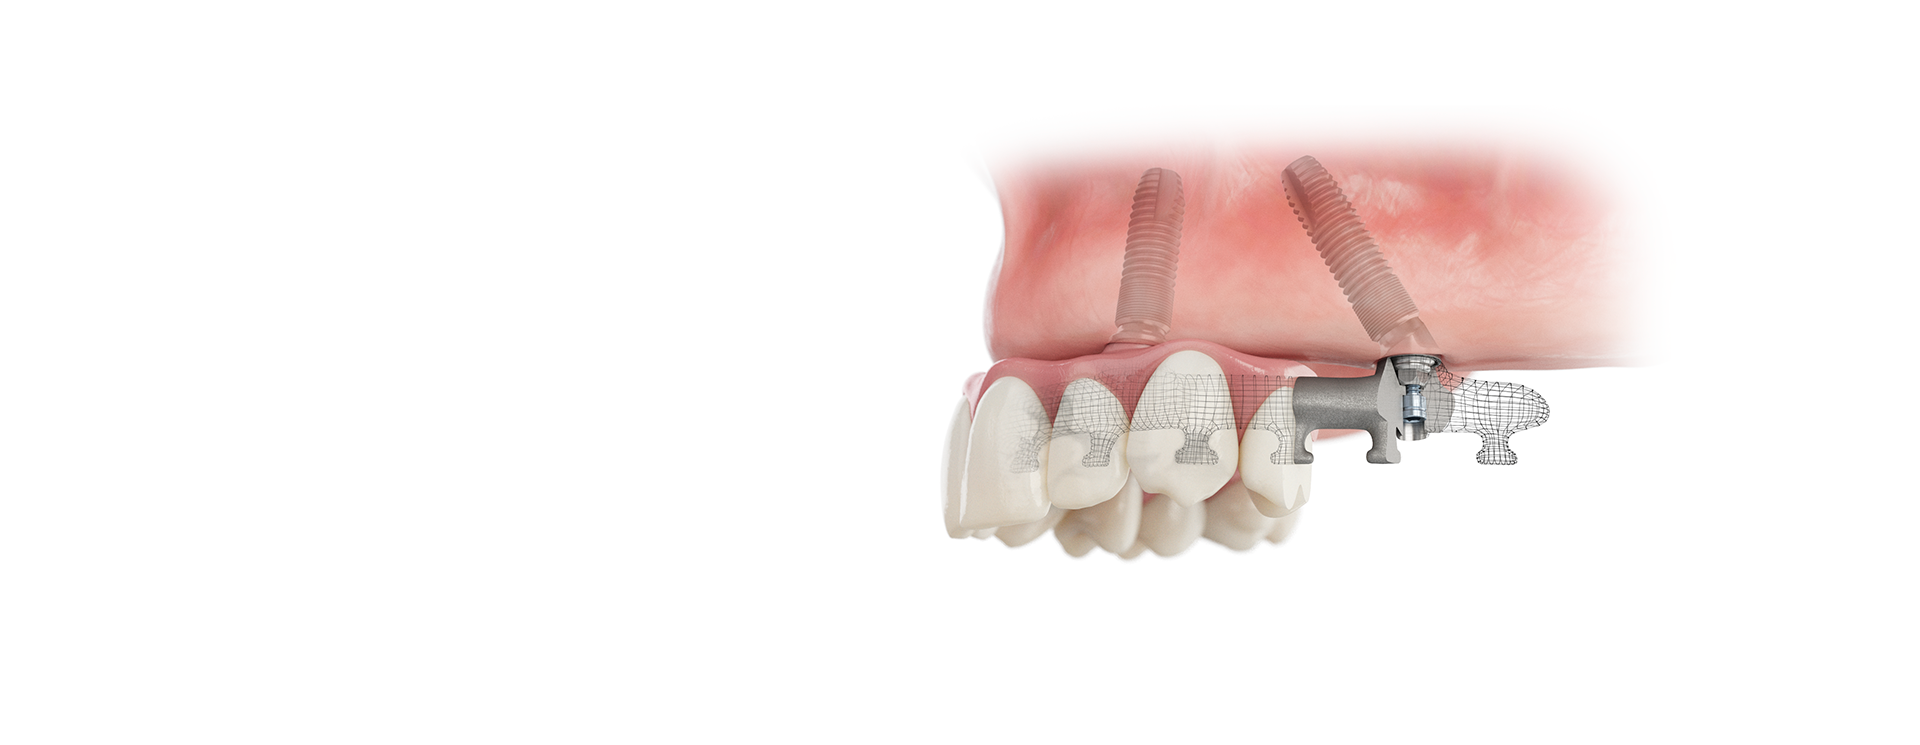

SmartFix Concept by Dentsply Sirona

The SmartFix concept allows for shorter treatment times, simplified procedures and streamlined workflows - without compromising reliable treatment outcomes for your edentulous patients.

The SmartFix concept provides edentulous, or soon-to-be edentulous, patients with an immediate, fixed restoration supported by only four implants

Implant-prosthetic procedure for the immediate restoration of an edentoulous patient using OsseoSpeed EV and Multibase Abutment EV.

Animation showing the easy seating of the Multibase Abutment EV 30° using the short and flexible holder.

Implant-prosthetic procedure for the immediate restoration of an edentoulous patient using OsseoSpeed Profile EV and Multibase Abutment EV.